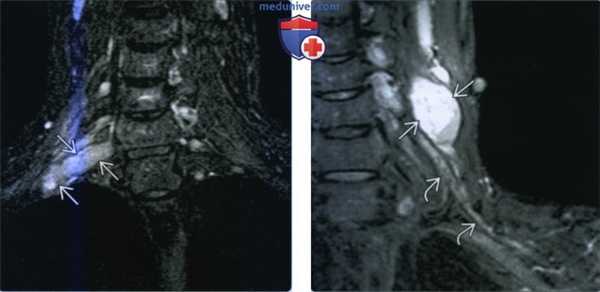

(Слева) STIR MPT, коронарная проекция (МР-нейрография). Асимметричное увеличение корешка CVIII нерва. выходящего между С7-Т1 позвонками.

(Справа) STIR MPT, коронарная проекция, другой пациент. Веретеннобразная шваннома с неоднородным гиперинтенсивным сигналом, расположенная в нижних отделах шеи. По сравнению с соседними нервами плечевого сплетения сигнал гораздо интенсивнее. При проведении тонкоигольной биопсии, благодаря которой удалось подтвердить диагноз, у пациента отмечалось подергивание руки.